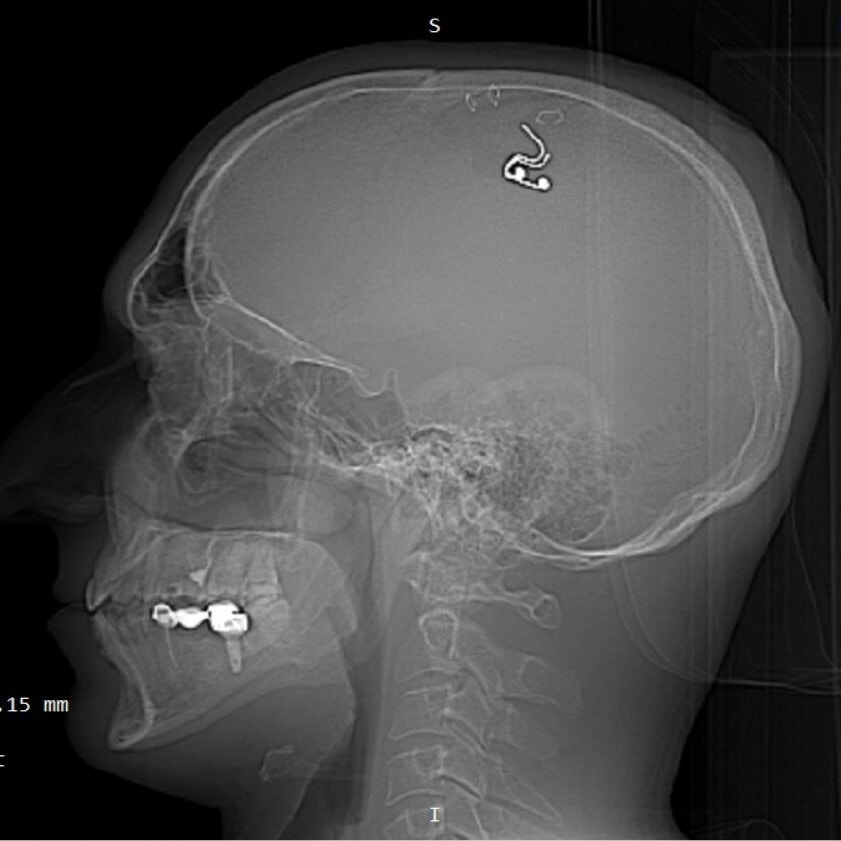

不愧是戰斗民族!來自俄羅斯、40歲的研究人員拉杜加(Michael Raduga)為了想要達成如科幻電影般“控制夢境”的目的,竟透過YouTube影片自學動手術,接著就在家自行動手術、嘗試將芯片植入大腦,導致嚴重失血險些喪命;拉杜加術後也透露,他在手術前就已經做好赴死的准備,對於手術後成功活下來感到相當興奮,事件公開後引起熱烈討論。

綜合《每日郵報》等外媒報道,作為研究員的拉杜加是俄羅斯某研究中心的創始人,著重在睡眠麻痹、靈魂出竅的體驗指導;而據了解,拉杜加壹直都想做到如同科幻電影《潛行空間》(Inception)劇情般,透過電極控制夢境,也因此在看過幾段YouTube影片、拿了5只羊練習後,拉杜加就著手開始了“自行開腦”的神經外科手術。

拉杜加在手術過程中,不僅用鑽頭推平了部分頭骨,還選擇用回紋針夾住掀開的皮膚,手法相當粗糙、更導致失血超過1公升險些危及生命。對此牛津大學神經外科醫生顧問格林(Alex Green)傻眼譴責這樣的行為,強調神經外科手術都是經驗豐富且合格的醫生才能執行,否則可能會因為皮質靜脈或腦內血管出血的發生,造成永久性功能障礙或死亡。